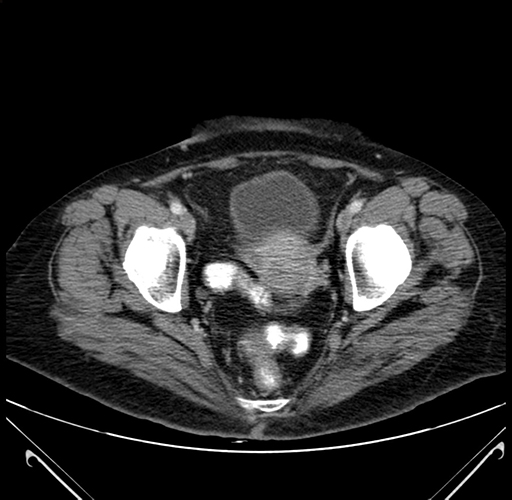

Pre-Chemo: Axial Venous

Axial Venous

Imaging analysis

Based on your CT findings, which issue(s) would give reason for "planned slowing down moment(s)" in this case?

Considering a standard right hepatectomy procedure, what step(s) of the operation would you do differently in this case?